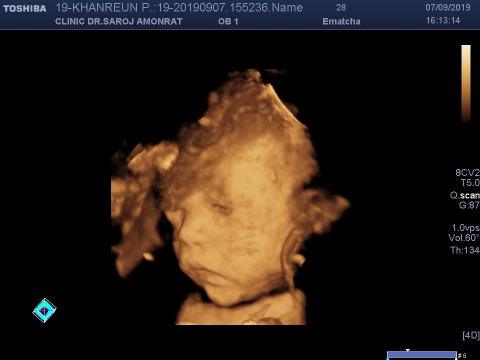

อายุครรถ์ 32วีค5วัน ผมหนัก 2,100 แล้วครับ ขอดูเด็กเดือน พย. น่ารักๆหน่อยครับ ผมไม่ชอบเลยเวลาคุณหมอซาวด์ หน้าจะบึ้งหน่อยๆ55555

ที่คลีนิคถ้าซาวด์4มิติ ได้คลิปและปริ้นรูป 2,500บาทค่ะ